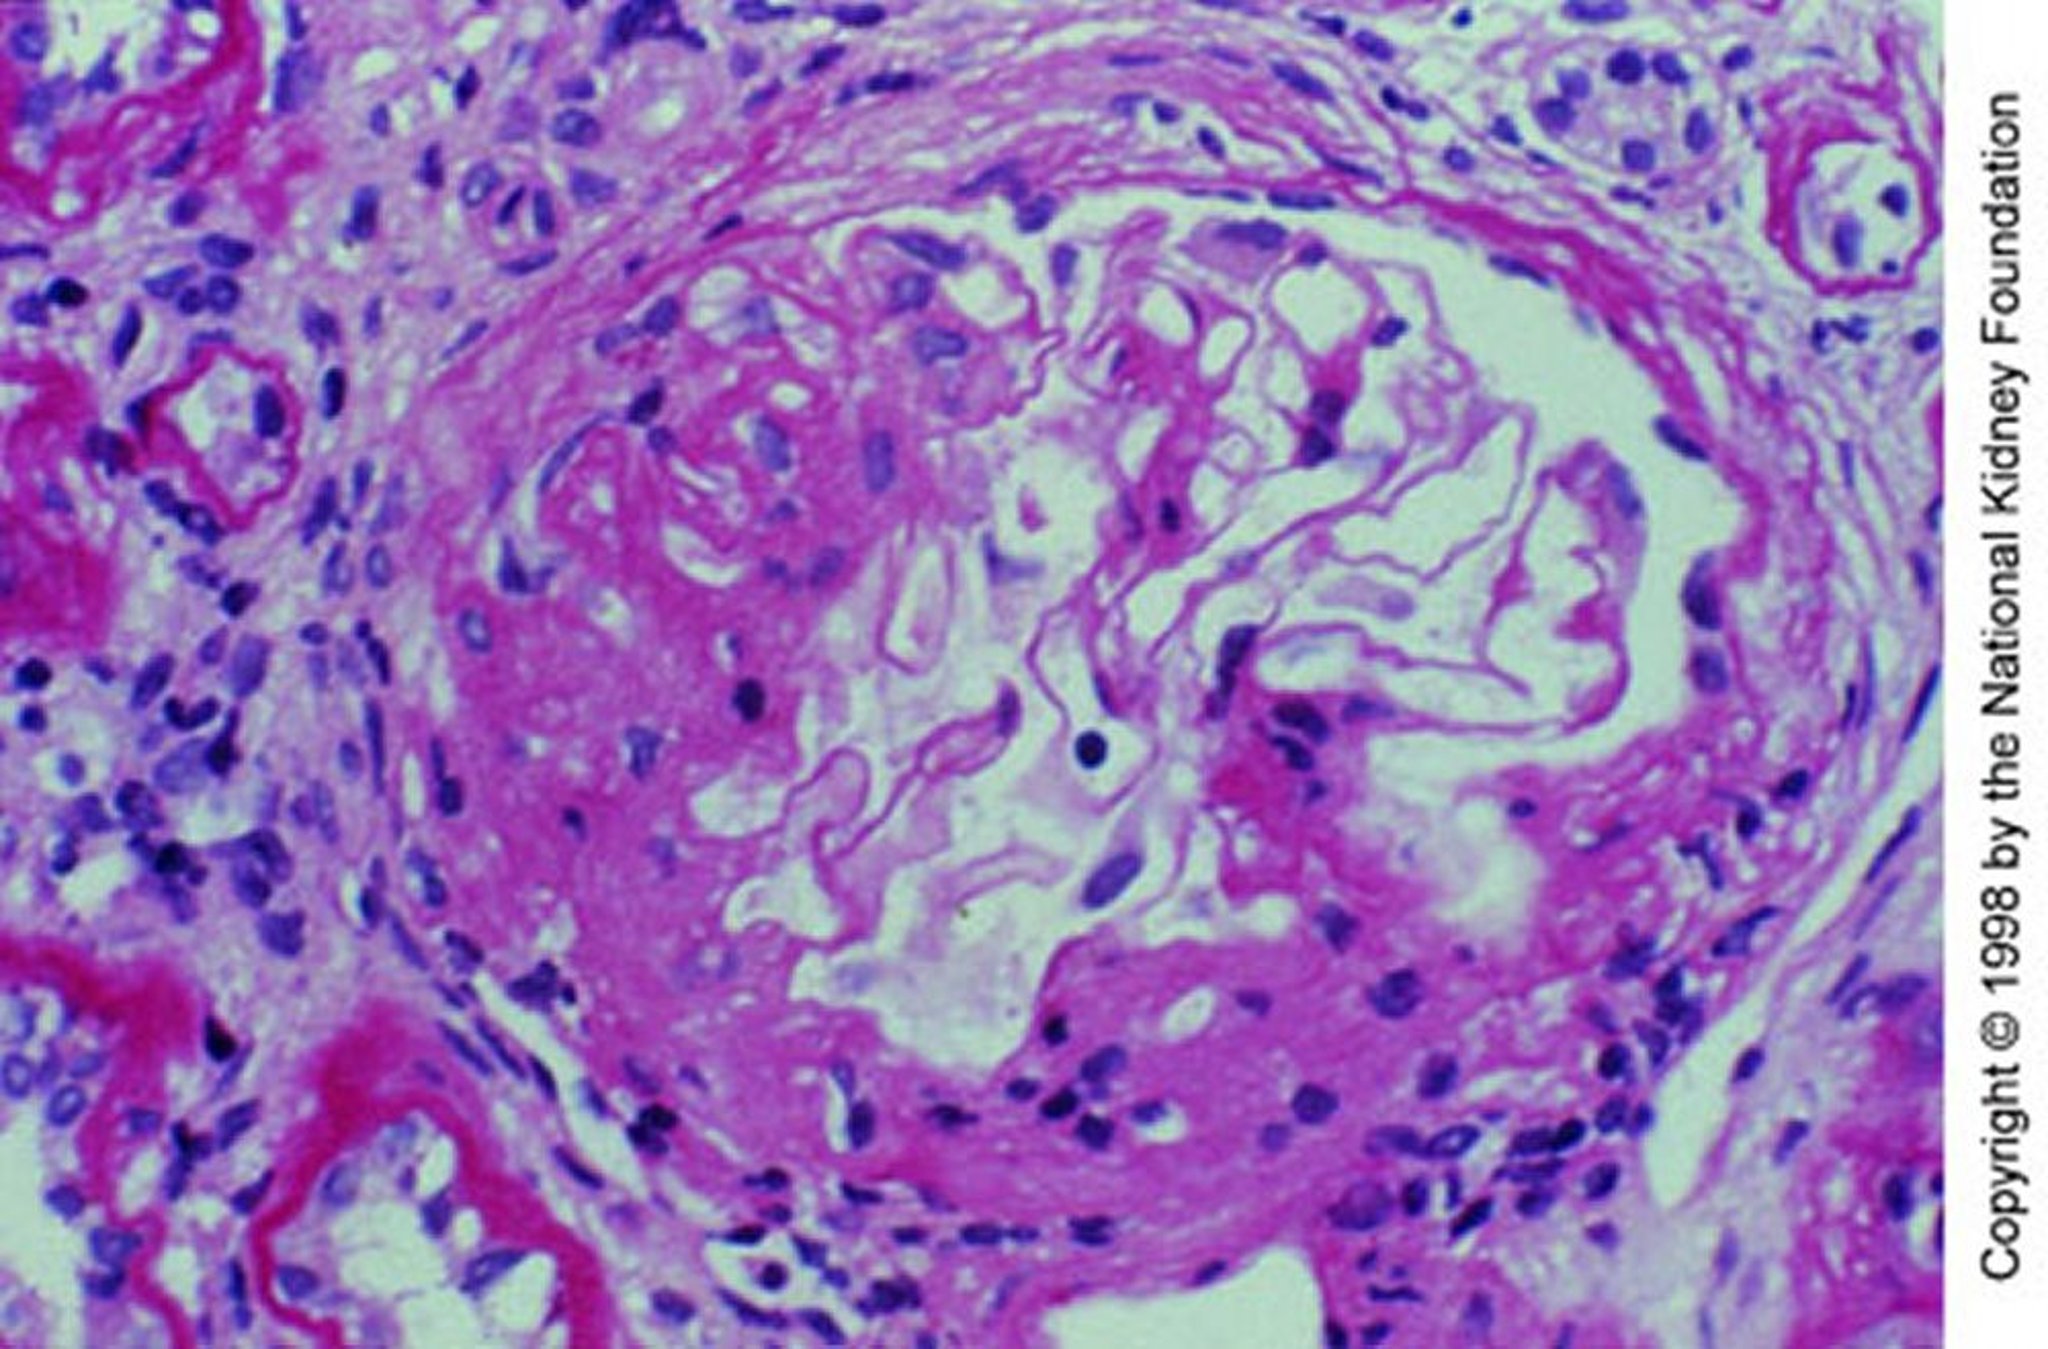

Nefropatia da IgA (espansione mesangiale)

Espansione mesangiale con sclerosi segmentaria (colorazione con acido periodico di Schiff, ×200).

Imagine fornita da Agnes Fogo, MD, and the American Journal of Kidney Diseases' Atlas of Renal Pathology (vedi www.ajkd.org).